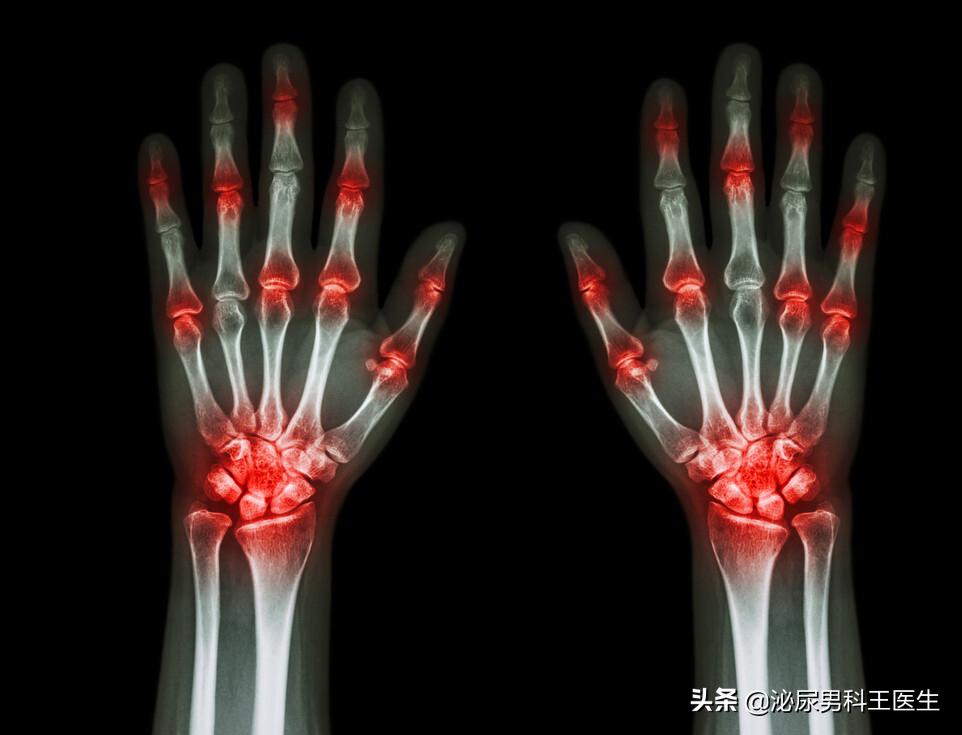

因为当人体内的尿酸过多时,尿酸结晶就会在人体的关节、组织中聚集,并引起严重的疼痛或者是其他严重疾病。

假如尿酸结晶聚集在关节中,患者一开始可能还感觉不到什么异常,但可能会在某个夜晚突然感到一个或是多个关节的剧痛,甚至出现关节的红肿、表皮温度升高等症状,这就说明患者已经得了痛风。

可持续的高尿酸会导致痛风的频繁、反复发作,还会令尿酸结晶在更多关节处堆积,导致痛风发作的“范围”越来越广。而且,尿酸结晶的不断堆积,会导致关节变形、影响关节的正常活动,更可能会影响人体的行动,大幅降低患者的生活质量。